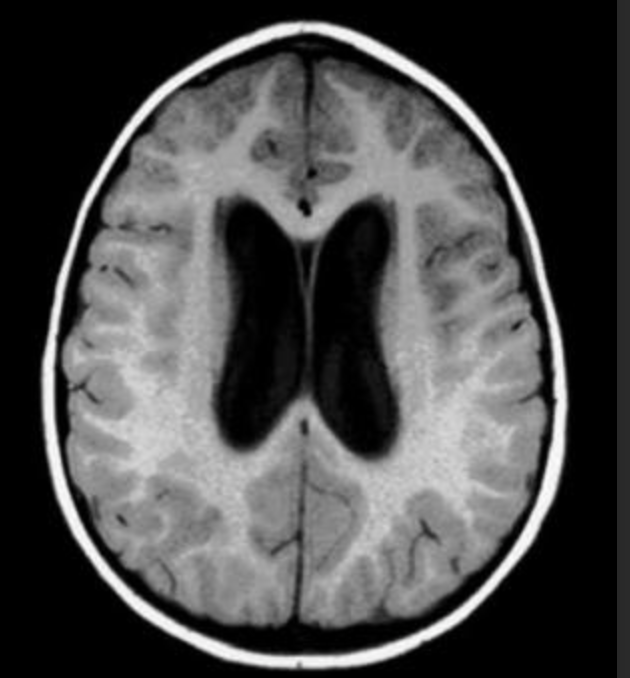

脑积水是神经外科常见的病症之一,是指颅内的脑脊液液体异常积聚,由于脑脊液的流动受阻或其产生与吸收不平衡引起,此外还有炎症反应、神经元损伤和室周轴突损害。

脑脊液生成过多、循环受阻、吸收障碍等,都可以导致脑脊液积蓄过多,使得颅内原本容纳脑脊液的空腔,如脑室系统和蛛网膜下腔,受到过多脑脊液的挤压而扩大,从而导致一类疾病的总称。临床表现为颅内压增高和脑功能损害。

A:脑脊液(Cerebro-Spinal Fluid,CSF)是环绕于中枢神经系统(脑和脊髓)周围的无色透明的液体,主要存在于颅内和脊柱内的空隙间,比如脑室、蛛网膜下腔和脊髓中央管内,生成,循环,然后再被吸收,其总量稳定保持在水平,时刻处在一种动态的平衡之中。它提供脑的一部分代谢功能,也在运动时像水床一样保护脑。正常成年人脑脊液量约100~150 mL。脑脊液生成速度大约0.3 mL/分钟,一天大约产生450 mL,也就是说每天至少要更换3次。

脑脊液主要由脑室中由血管组织盘绕成的结构——脉络丛产生,当血液流经此处时时,血液中的一部分成分“渗出”,形成脑脊液。脑脊液不是一潭死水,而是不断生成和被吸收,因此处于循环之中,这个循环受阻,是脑积水的重要原因。

脑内有不少空隙,脑脊液在其中流动,包括侧脑室、室间孔、三脑室、中脑导水管、四脑室、正中孔、外侧孔,较后流入脑和脊髓的蛛网膜下腔,准备吸收。